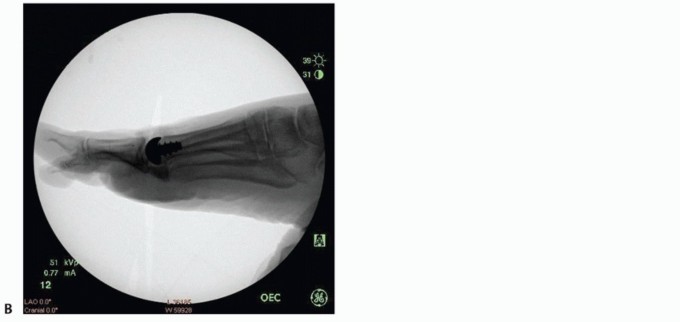

Obtain final AP and lateral fluoroscopic images to confirm alignment of the HemiCAP DF device. A maximally dorsiflexed lateral view may also be obtained (TECH FIG 9).

- TECH FIG 9 • Intraoperative fluoroscopic views following HemiCAP DF resurfacing. A. AP view. B. Lateral view neutral. C. Lateral view dorsiflexion.